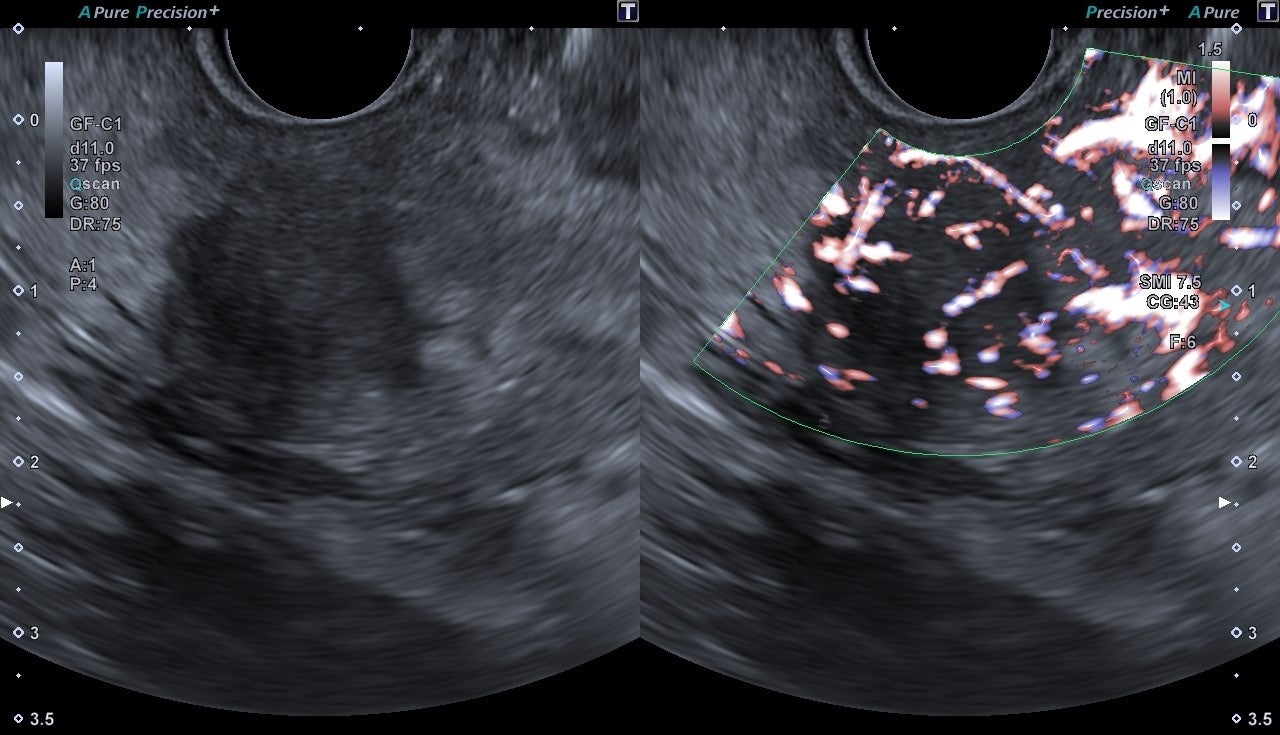

EUSをサポートする多彩な機能を搭載することで、信頼性の高い診断・治療方針の決定をサポートします。キヤノンメディカル独自技術であるSMI(Superb Micro-vascular Imaging)は、微細で低速な血流を捉える血流イメージングです。カラードプラ※1は描出困難であった低流速血流を高感度、高分解能、高フレームレート※2、低アーチファクト※3に描出できるため、超音波画像下で穿刺を行う場合でも、より安全な手技をサポートします。また、EUSで病変の炎症度や良悪性などを診断する際、病変組織の硬さに関する情報が重要な判断材料になります。SWE(Shear Wave Elastography)は組織の硬さを数値やカラーマップで表示する技術のため、より客観的な硬さの評価が可能です。

SMI SWE